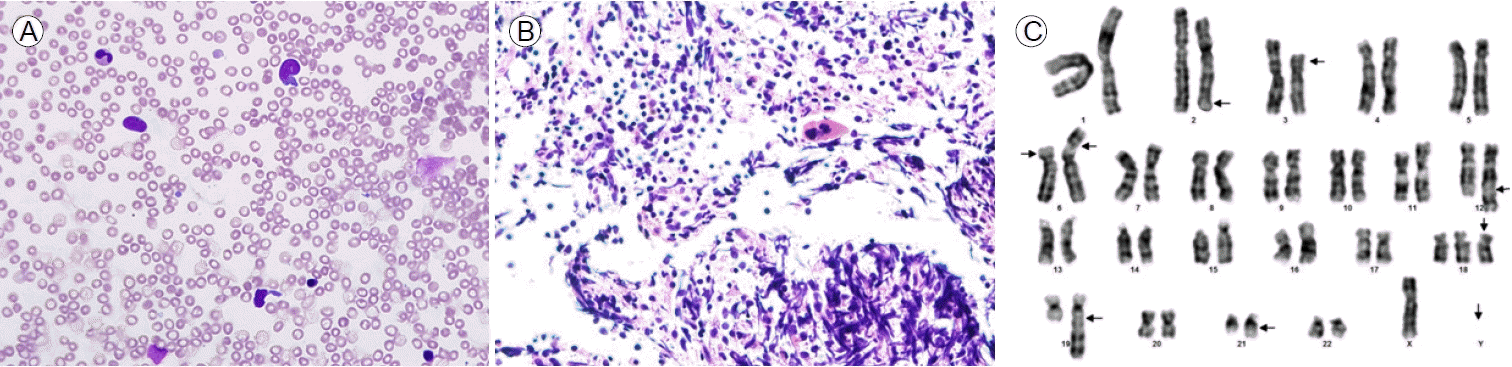

Figure 1.

(A) Bone marrow aspirate smear showing predominantly blast cells (hematoxylin and eosin stain [H&E], ×400). (B) Bone marrow core biopsy section demonstrating markedly hypercellular bone marrow containing predominantly blast cells (H&E, ×400). (C) Giemsa banding karyogram: complex karyotype.